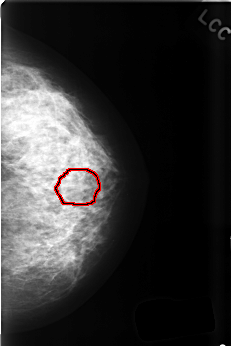

C_0412_1.LEFT_CC

LEFT_CC LINES 4496 PIXELS_PER_LINE 2992 BITS_PER_PIXEL 12 RESOLUTION 50 OVERLAY

FILE: C_0412_1.LEFT_CC.OVERLAY

TOTAL_ABNORMALITIES 1

ABNORMALITY 1

LESION_TYPE MASS SHAPE ROUND MARGINS CIRCUMSCRIBED

ASSESSMENT 3

SUBTLETY 3

PATHOLOGY BENIGN

TOTAL_OUTLINES 1

BOUNDARY